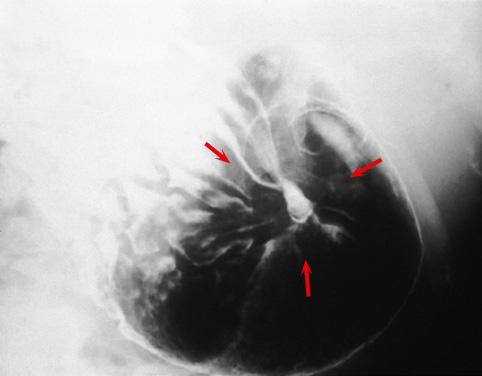

疾患(病理主体)の分類悪性上皮性腫瘍/印環細胞癌

部位(臓器別)胃(部位)/胃角

検査方法X-P

腫瘍の肉眼分類0型(表在型)/IIc型(IIc+III)

病変の最大径(ミリ)30〜34

腫瘍の深達度m